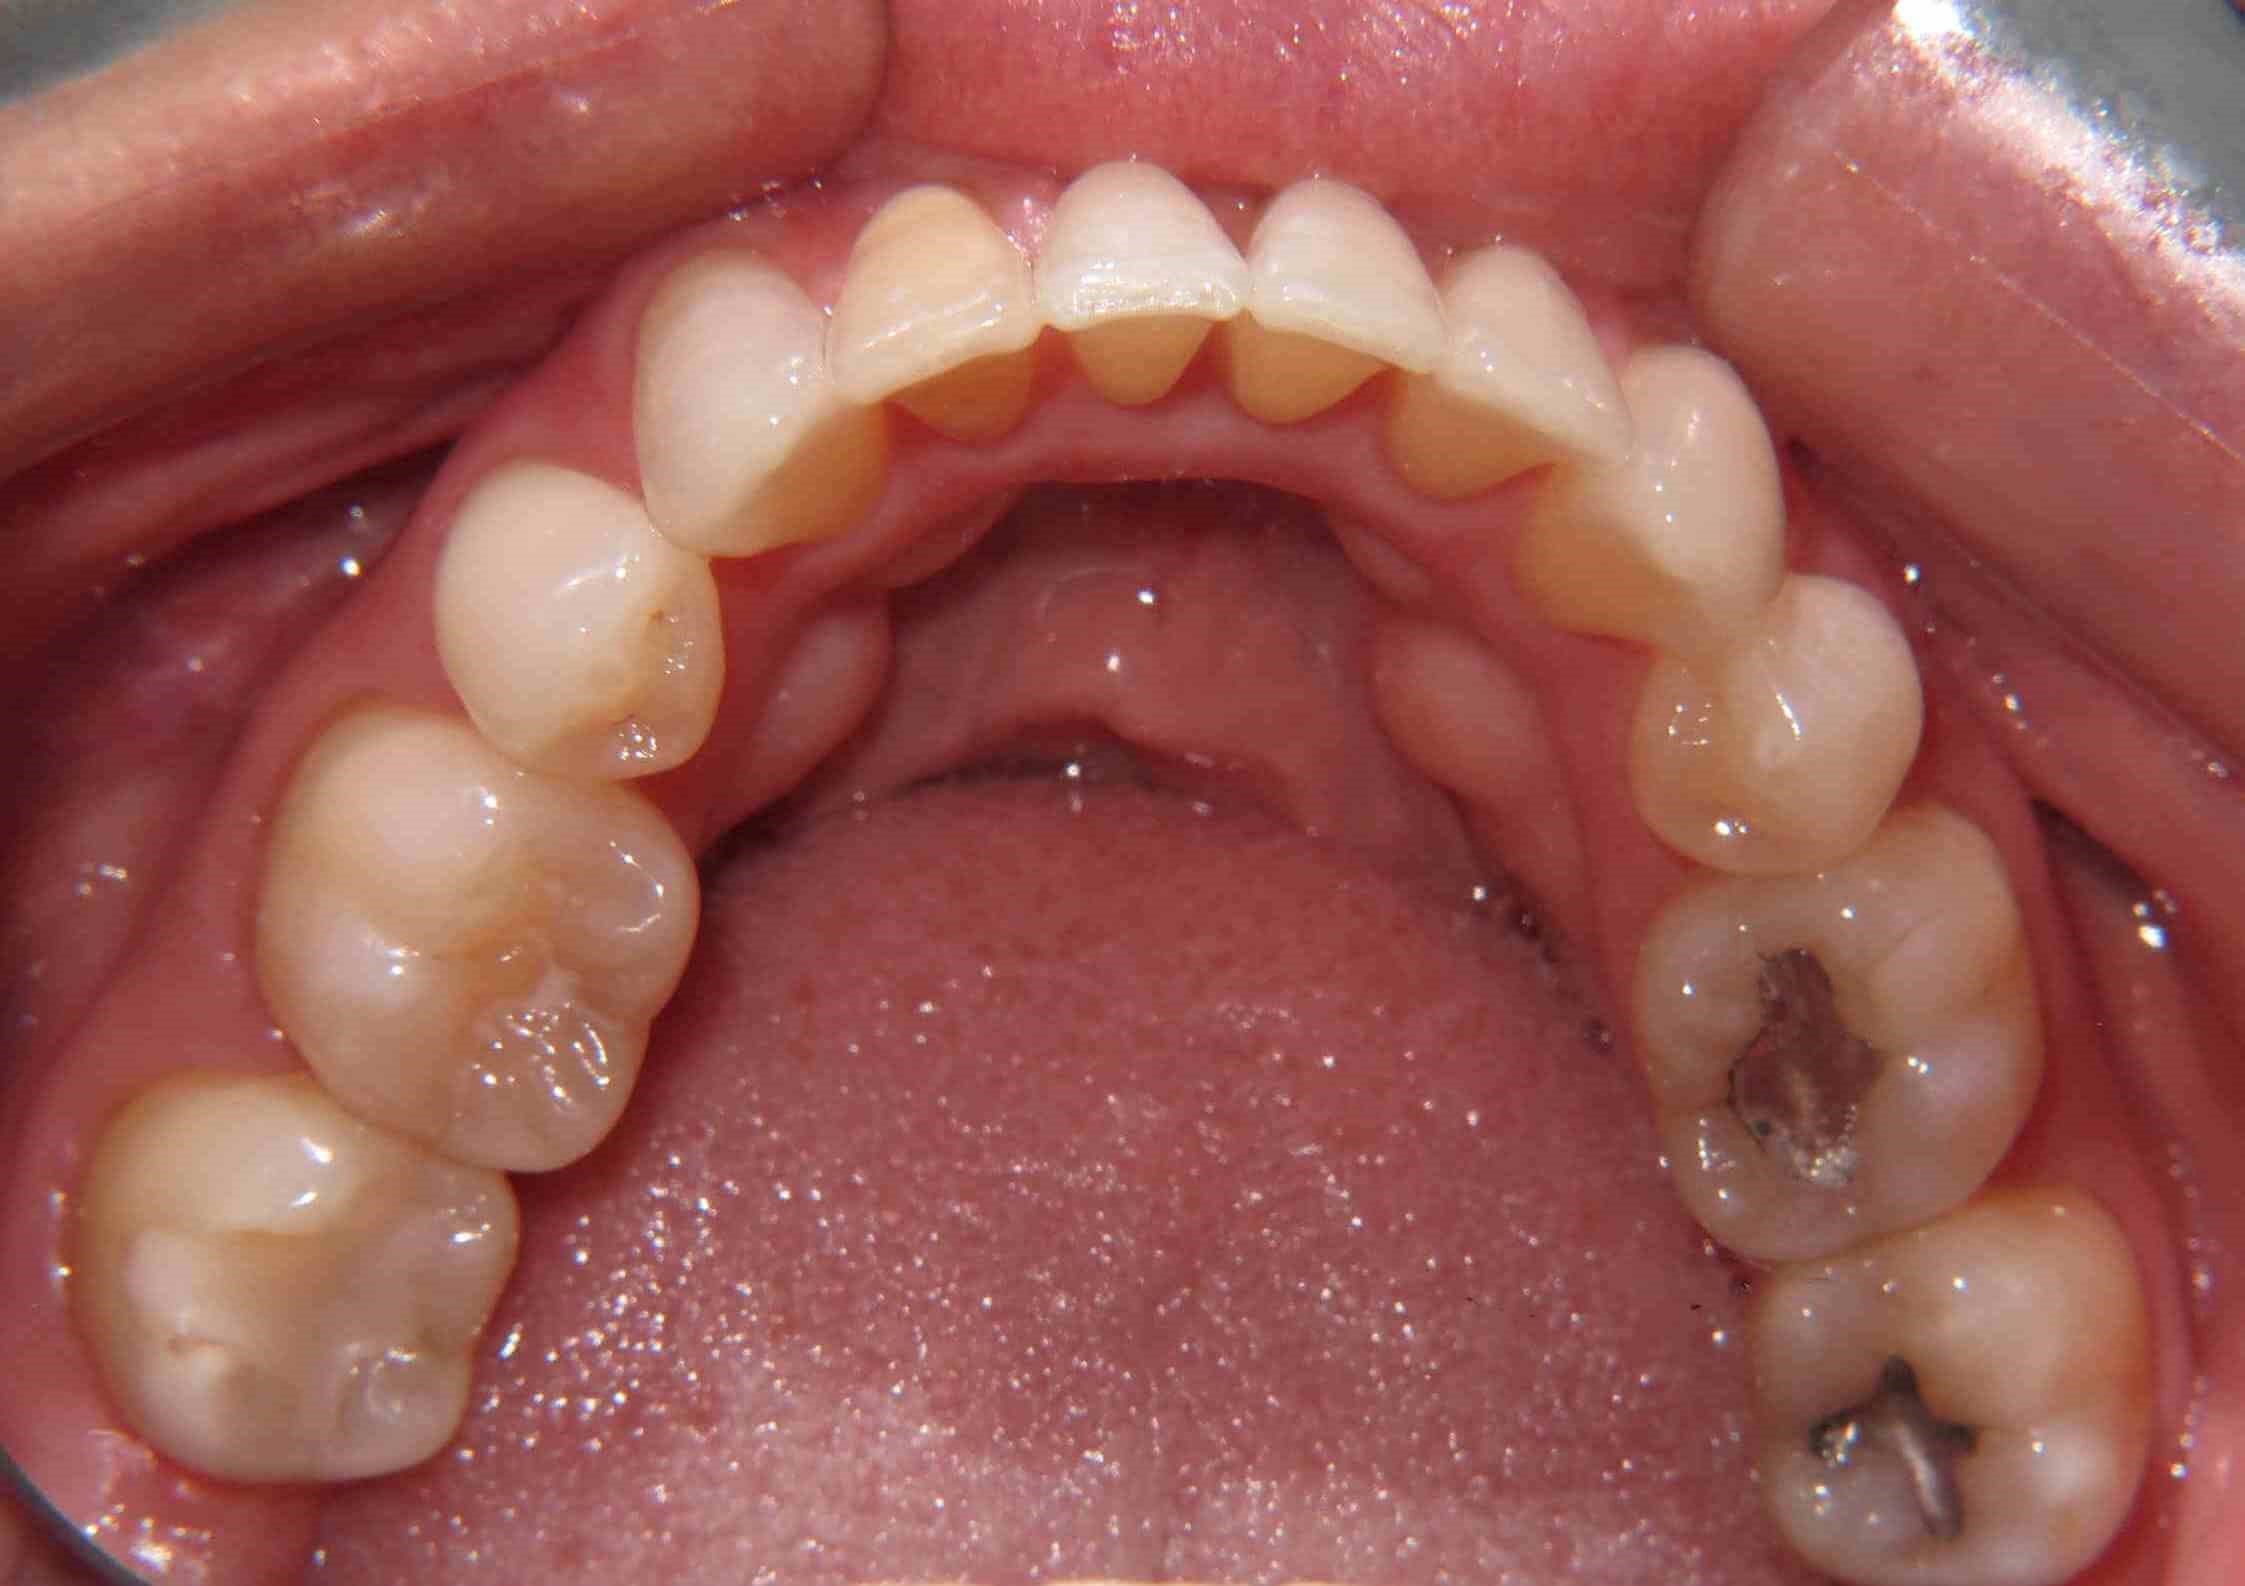

Female from Plano, TX gets Clear Correct Aligner Therapy now has great smile!